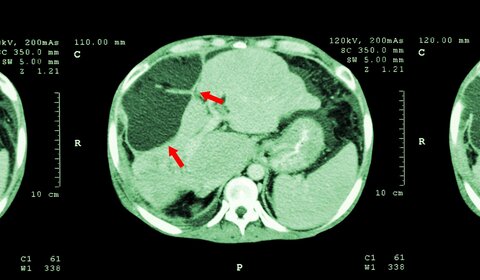

Hitting the target for cancer

For many years molecular radiotherapy (MRT) has been used for palliative care of cancer patients, but it has great potential to become a potent first line cancer treatment. The therapy uses radioactive drugs to target specific tumour locations, for example by injection of radioactive microspheres into tumours in the liver via its artery. Currently...

Traceability Boosts Cancer Therapy

For many years molecular radiotherapy, MRT, has been used for palliative cancer care, but it has great potential to become a potent first line cancer treatment. The therapy uses radioactive drugs to target specific tumours, for example radioactive yittrium-90 microspheres are used to treat liver cancers. However, accurate activity measurements of ...